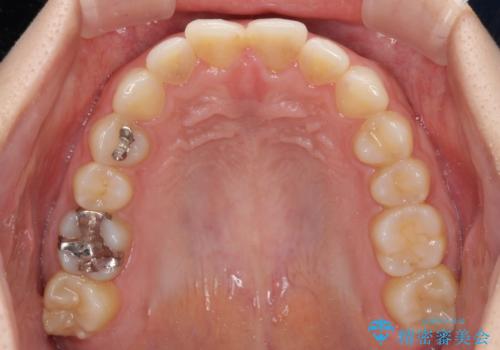

- 以前の矯正治療の後戻りを気にして来院された患者様です。

下顎前歯にデコボコがあるため、ワイヤー矯正により改善することとしました。

もう少しデコボコを改善したかったのですが、ご本人の希望もあり、装置を除去しました。

後戻りを防止するため、舌側を細いワイヤーによる保定を行いました。